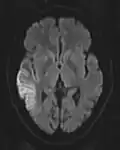

The most common application of conventional DWI (without DTI) is in acute brain ischemia. DWI directly visualizes the ischemic necrosis in cerebral infarction in the form of a cytotoxic edema,[38] appearing as a high DWI signal within minutes of arterial occlusion.[39] With perfusion MRI detecting both the infarcted core and the salvageable penumbra, the latter can be quantified by DWI and perfusion MRI.[40]

-

DWI showing restricted diffusion in the medial dorsal thalami consistent with Wernicke encephalopathy -

DWI showing cortical ribbon-like high signal consistent with diffusion restriction in a patient with known MELAS syndrome

Cerebral infarction leads to diffusion restriction, and the difference between images with various DWI weighting will therefore be minor, leading to an ADC image with low signal in the infarcted area.[24] A decreased ADC may be detected minutes after a cerebral infarction.[26] The high signal of infarcted tissue on conventional DWI is a result of its partial T2 weighting.[27]